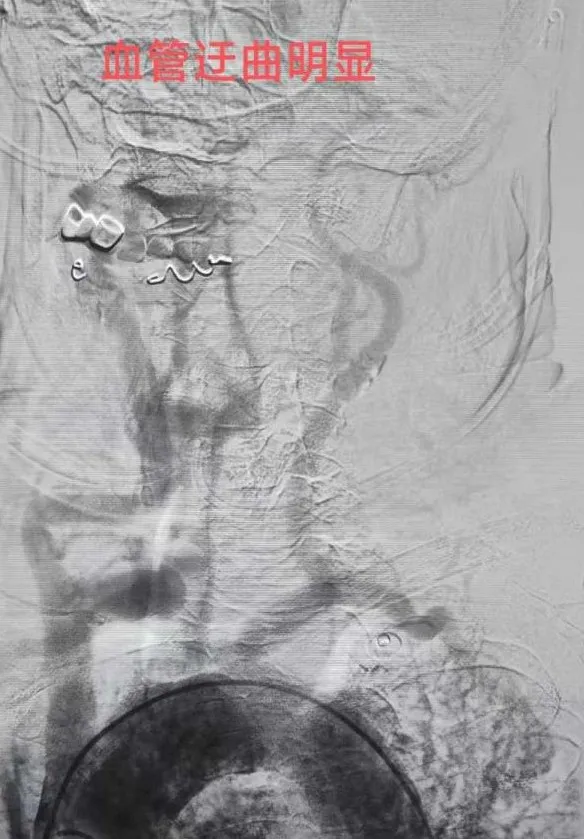

“必须立即进行脑动脉取栓手术!”神经内科王文杰主任了解患者详情后当机立断。与家属充分沟通并获得同意后,患者被迅速送入介入治疗室。术中造影显示,患者右侧大脑中动脉M1末端完全闭塞。术中造影发现患者多发动脉硬化、狭窄,血管迂曲明显,情况复杂,手术难度较高。且患者病情进展加重,王文杰、于弋水决定在局麻下为患者急诊动脉机械取栓。根据患者血管特点,选用合适导管行“血栓抽吸术”,仅一次操作即完整取出暗红色血栓,原闭塞血管血流瞬间恢复至最高分级(mTICI 3级),从穿刺到血管完全再通仅用50分钟。